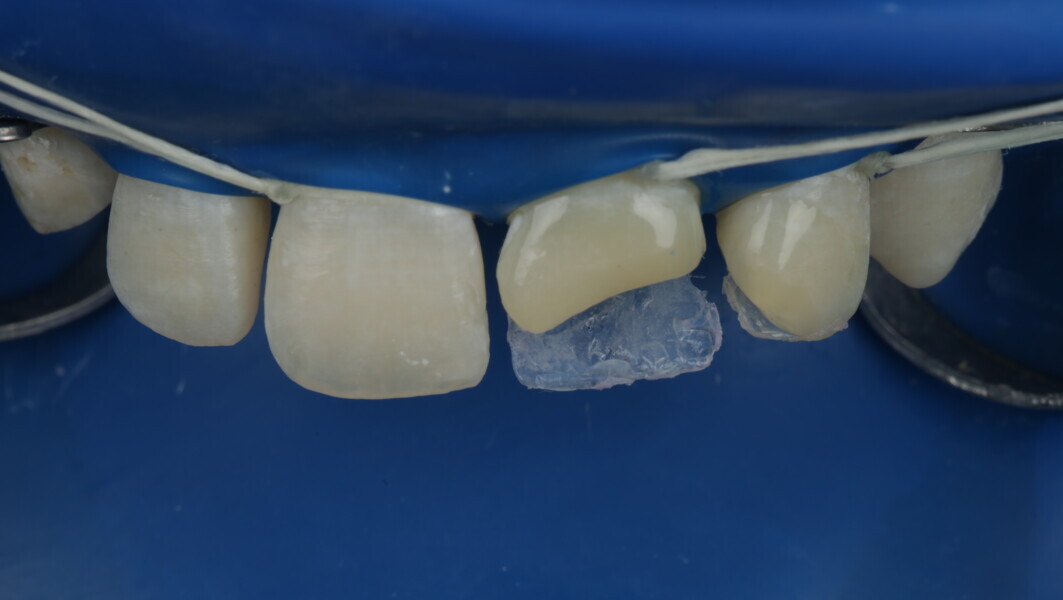

A 10-year-old male patient reported with a complaint of trauma to the upper left central and lateral incisors, involving the enamel and dentin. Direct composite was used in multi-layers and the smile was restored. This article explains detailed steps in the polychromatic layering technique with special emphasis on the finishing and polishing protocol. 3M Espe Filtex Z350 Xt was used with a universal bonding agent.

Fig 19-24: Contact build-up with band and wedge